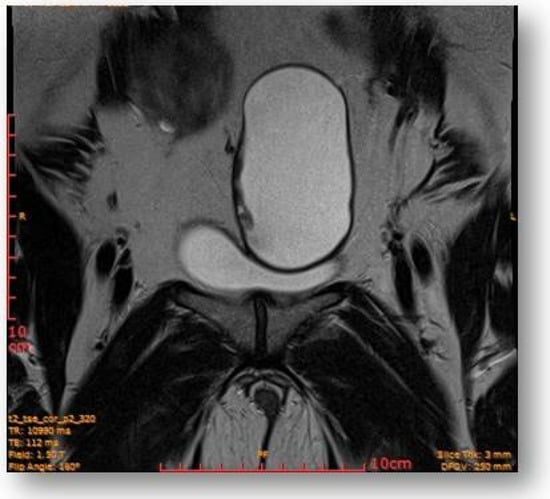

Considering all the information gathered, we first decided to perform an ultrasound (US) which revealed a large hypoechoic cystic formation on the left of the uterus, misdiagnosed as a paraovarian cyst measuring 80 mm (Figure 1, Figure 2, Figure 3 and Figure 4).

Large hypoechoic cystic formation located to the left of the uterus measuring 80 mm.

The subsequent MRI revealed slight motion artifacts due to intestinal peristalsis.

The bladder had homogeneous content, without intraluminal protruding formations; imprinting of the medial and left-sided bladder dome by the dominant left adnexal lesion.